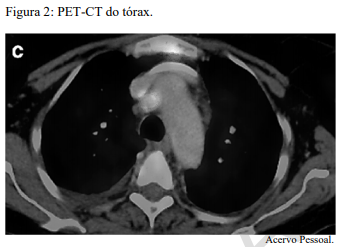

Um paciente de 62 anos de idade, tabagista ativo, cerca de 180 anos-maço, queixa-se de cansaço, tosse seca e perda de peso; por isso, procurou atendimento médico. O paciente referiu que pesava 100 kg e perdeu 10 kg. Realizou-se tomografia computadorizada de tórax, com evidência de lesão sólida de 2,1 cm em topografia de lobo inferior à direita, sólida, espiculada, com margens bem definidas e densidade de partes moles, assim como linfonodomegalia paratraqueal direita de 1,5 cm, paratraqueal esquerda de 1,2 cm e subcarinal de 2 cm. O paciente foi submetido a PET-CT de corpo inteiro, com evidência de hipercaptação de radiofármaco pela lesão (SUV 12) e eplo linfonodo representado na figura 2 a seguir.